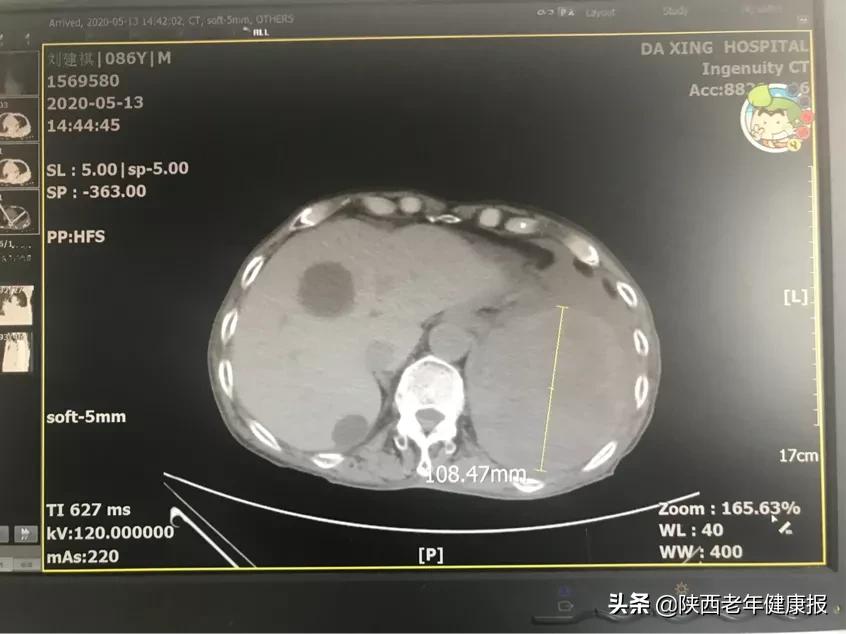

入住西安大兴医院胸肺疾病中心后,复查CT,发现胸腔内可疑巨大占位性病变,性质尚不明确,胸外科主任王律与麻醉科协同评估病情后决定胸腔镜探查。

手术中,王律主任行胸腔镜探查发现患者胸腔内有巨大的球形肿物,直径约10cm,大小约为成人心脏一般,并侵犯膈肌、纵膈及肺,怀疑为恶性肿瘤。面对如此大的球形肿物,只得进行开胸,小切口在胸腔镜辅助下切除肿瘤。